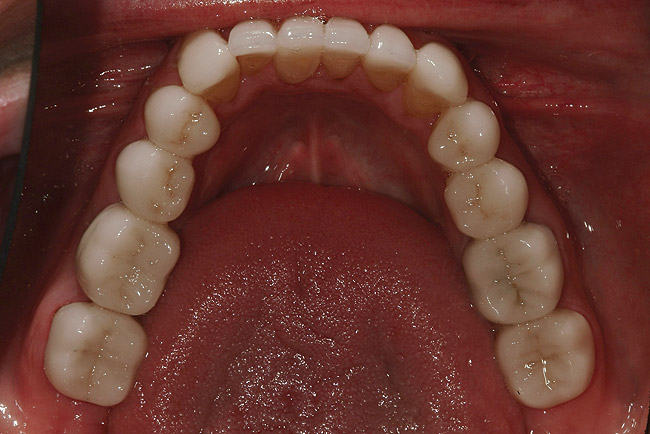

Figure 39: Maxillary postoperative view of the IPS e.max restorations.

Figure 39

Seating the Restorations

After viewing the final restorations when tried-in intraorally in various lighting conditions, including natural sunlight, the patient was pleased with the results. Proper adhesive protocols were then followed to definitively seat the restorations (Figure 30. through Figure 32.). Bisco adhesive All-Bond 3® (BISCO, www.bisco.com) was used for adhering the restorations, and Variolink® Veneer (Ivoclar Vivadent) cement was used for bonding the teeth. The molars remained out of occlusion at this point because they were included in the planned final treatment stage. The remaining stages of the full-mouth reconstruction (ie, phase 2—teeth Nos. 20 through 29, and phase 3—the molars) were completed according to the same procedures (Figure 33 through Figure 35.). Upon conclusion of the case, the patient, dentist, and ceramist were pleased with the esthetic and functional treatment results (Figure 36. through Figure 44).